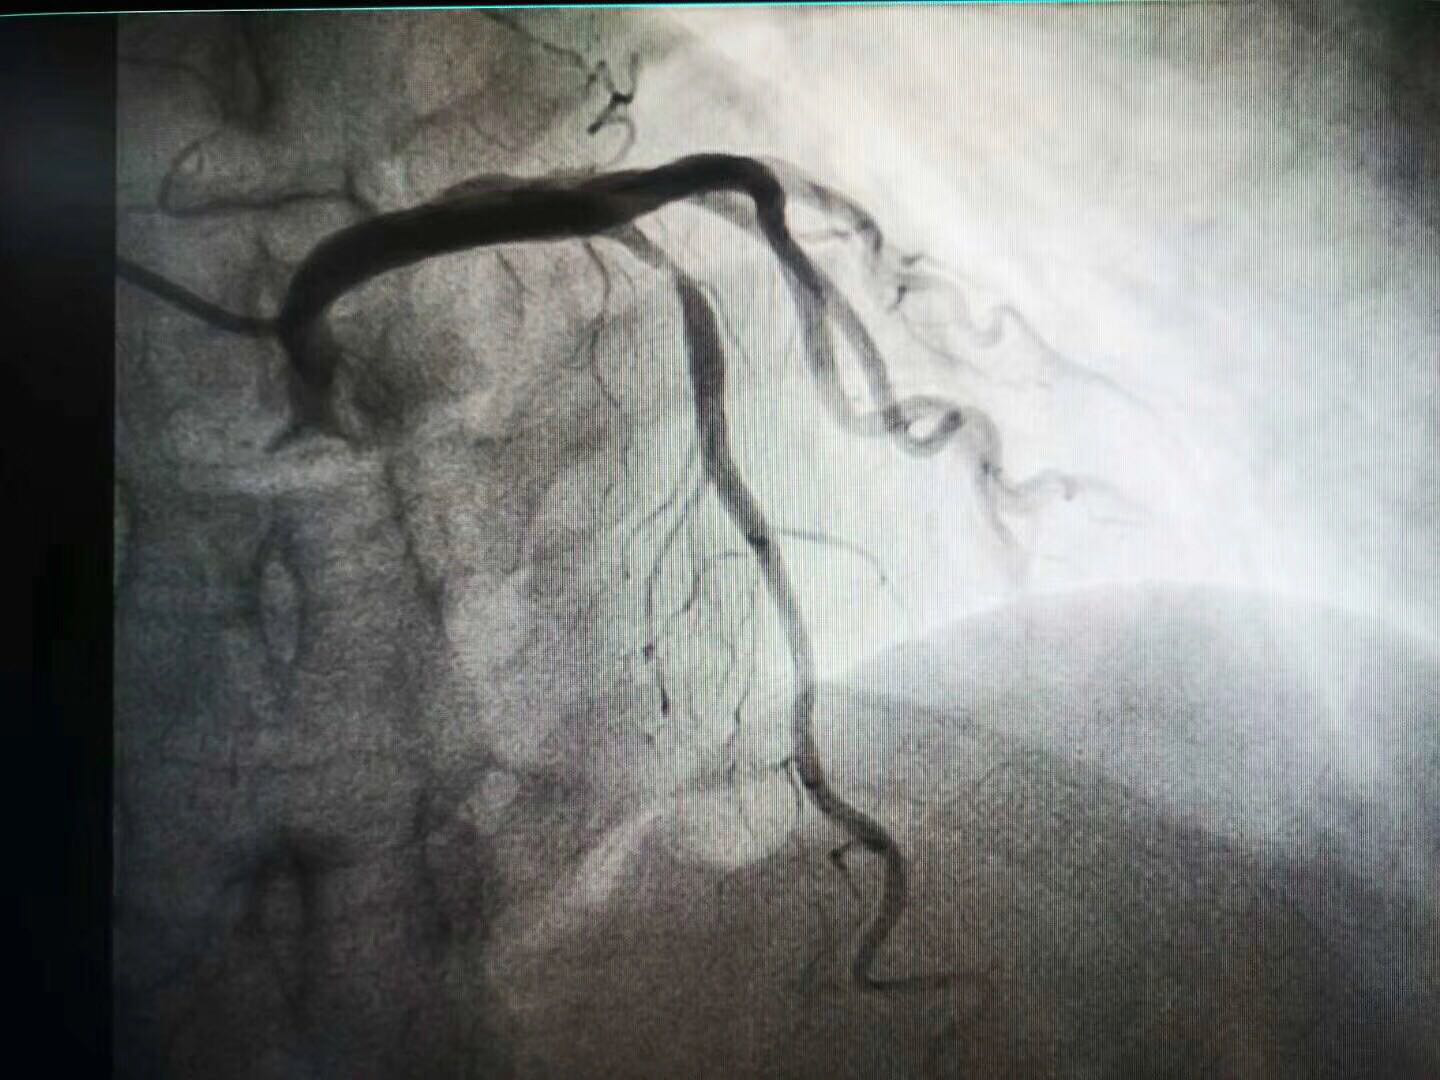

该患者为女性,年龄64岁,患者因“不稳定性心绞痛”多次就诊,饱受病痛折磨。本次就诊我院后,完善冠状动脉造影示LAD近段80%重度狭窄,在副院长白锋带领下,治疗团队严格把握适应症,和患者反复沟通后,最终于病变处成功植入3.5*21mmNeoVas生物可吸收支架,手术准备充分,术中严格执行PSP技术,术后经IVUS证实支架释放完美。生物可吸收支架是目前全球的研究热点,给冠心病患者治疗带来了新希望,避免金属植入物永存体内,恢复血管舒缩功能,避免金属牢笼禁锢,利于再次介入治疗,实现从“血管再通”到“血管再造”的新蜕变。